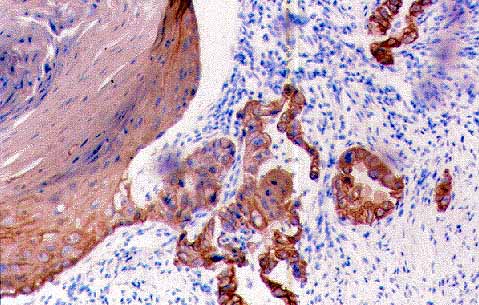

Figura 8:CK5D3 positivo en el componente adenomatoide del carcinoma (IHQx20).

figura 9

Figura 9:CK 14 positivo en el componente escamoso del carcinoma (IHQx20)